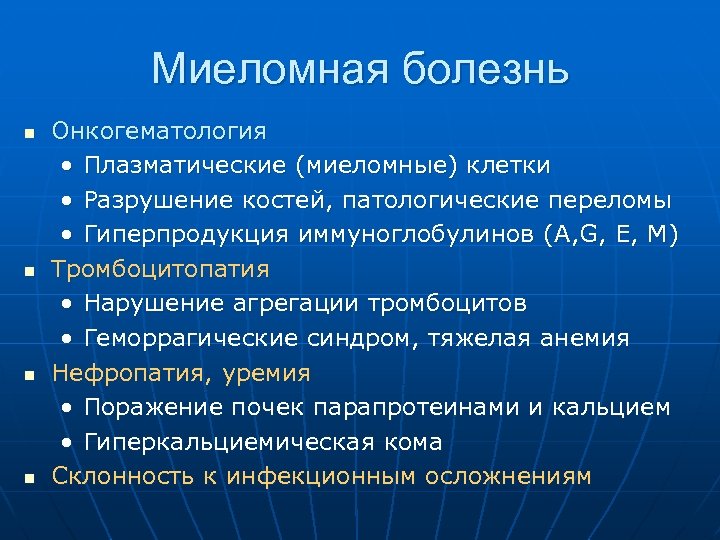

Миеломная болезнь n n Онкогематология • Плазматические (миеломные) клетки • Разрушение костей, патологические переломы • Гиперпродукция иммуноглобулинов (A, G, E, M) Тромбоцитопатия • Нарушение агрегации тромбоцитов • Геморрагические синдром, тяжелая анемия Нефропатия, уремия • Поражение почек парапротеинами и кальцием • Гиперкальциемическая кома Склонность к инфекционным осложнениям

Миеломная болезнь n Лечение: • Плазмаферез (удаление макроглобулинов) • Преднизолон до 200 мг/сут n • Химитерапия Нет специфических противопоказаний к оперативному лечению! • НО – риск вторичной инфекции и склонность к ее генерализации (иммуноглобулины неполноценны)